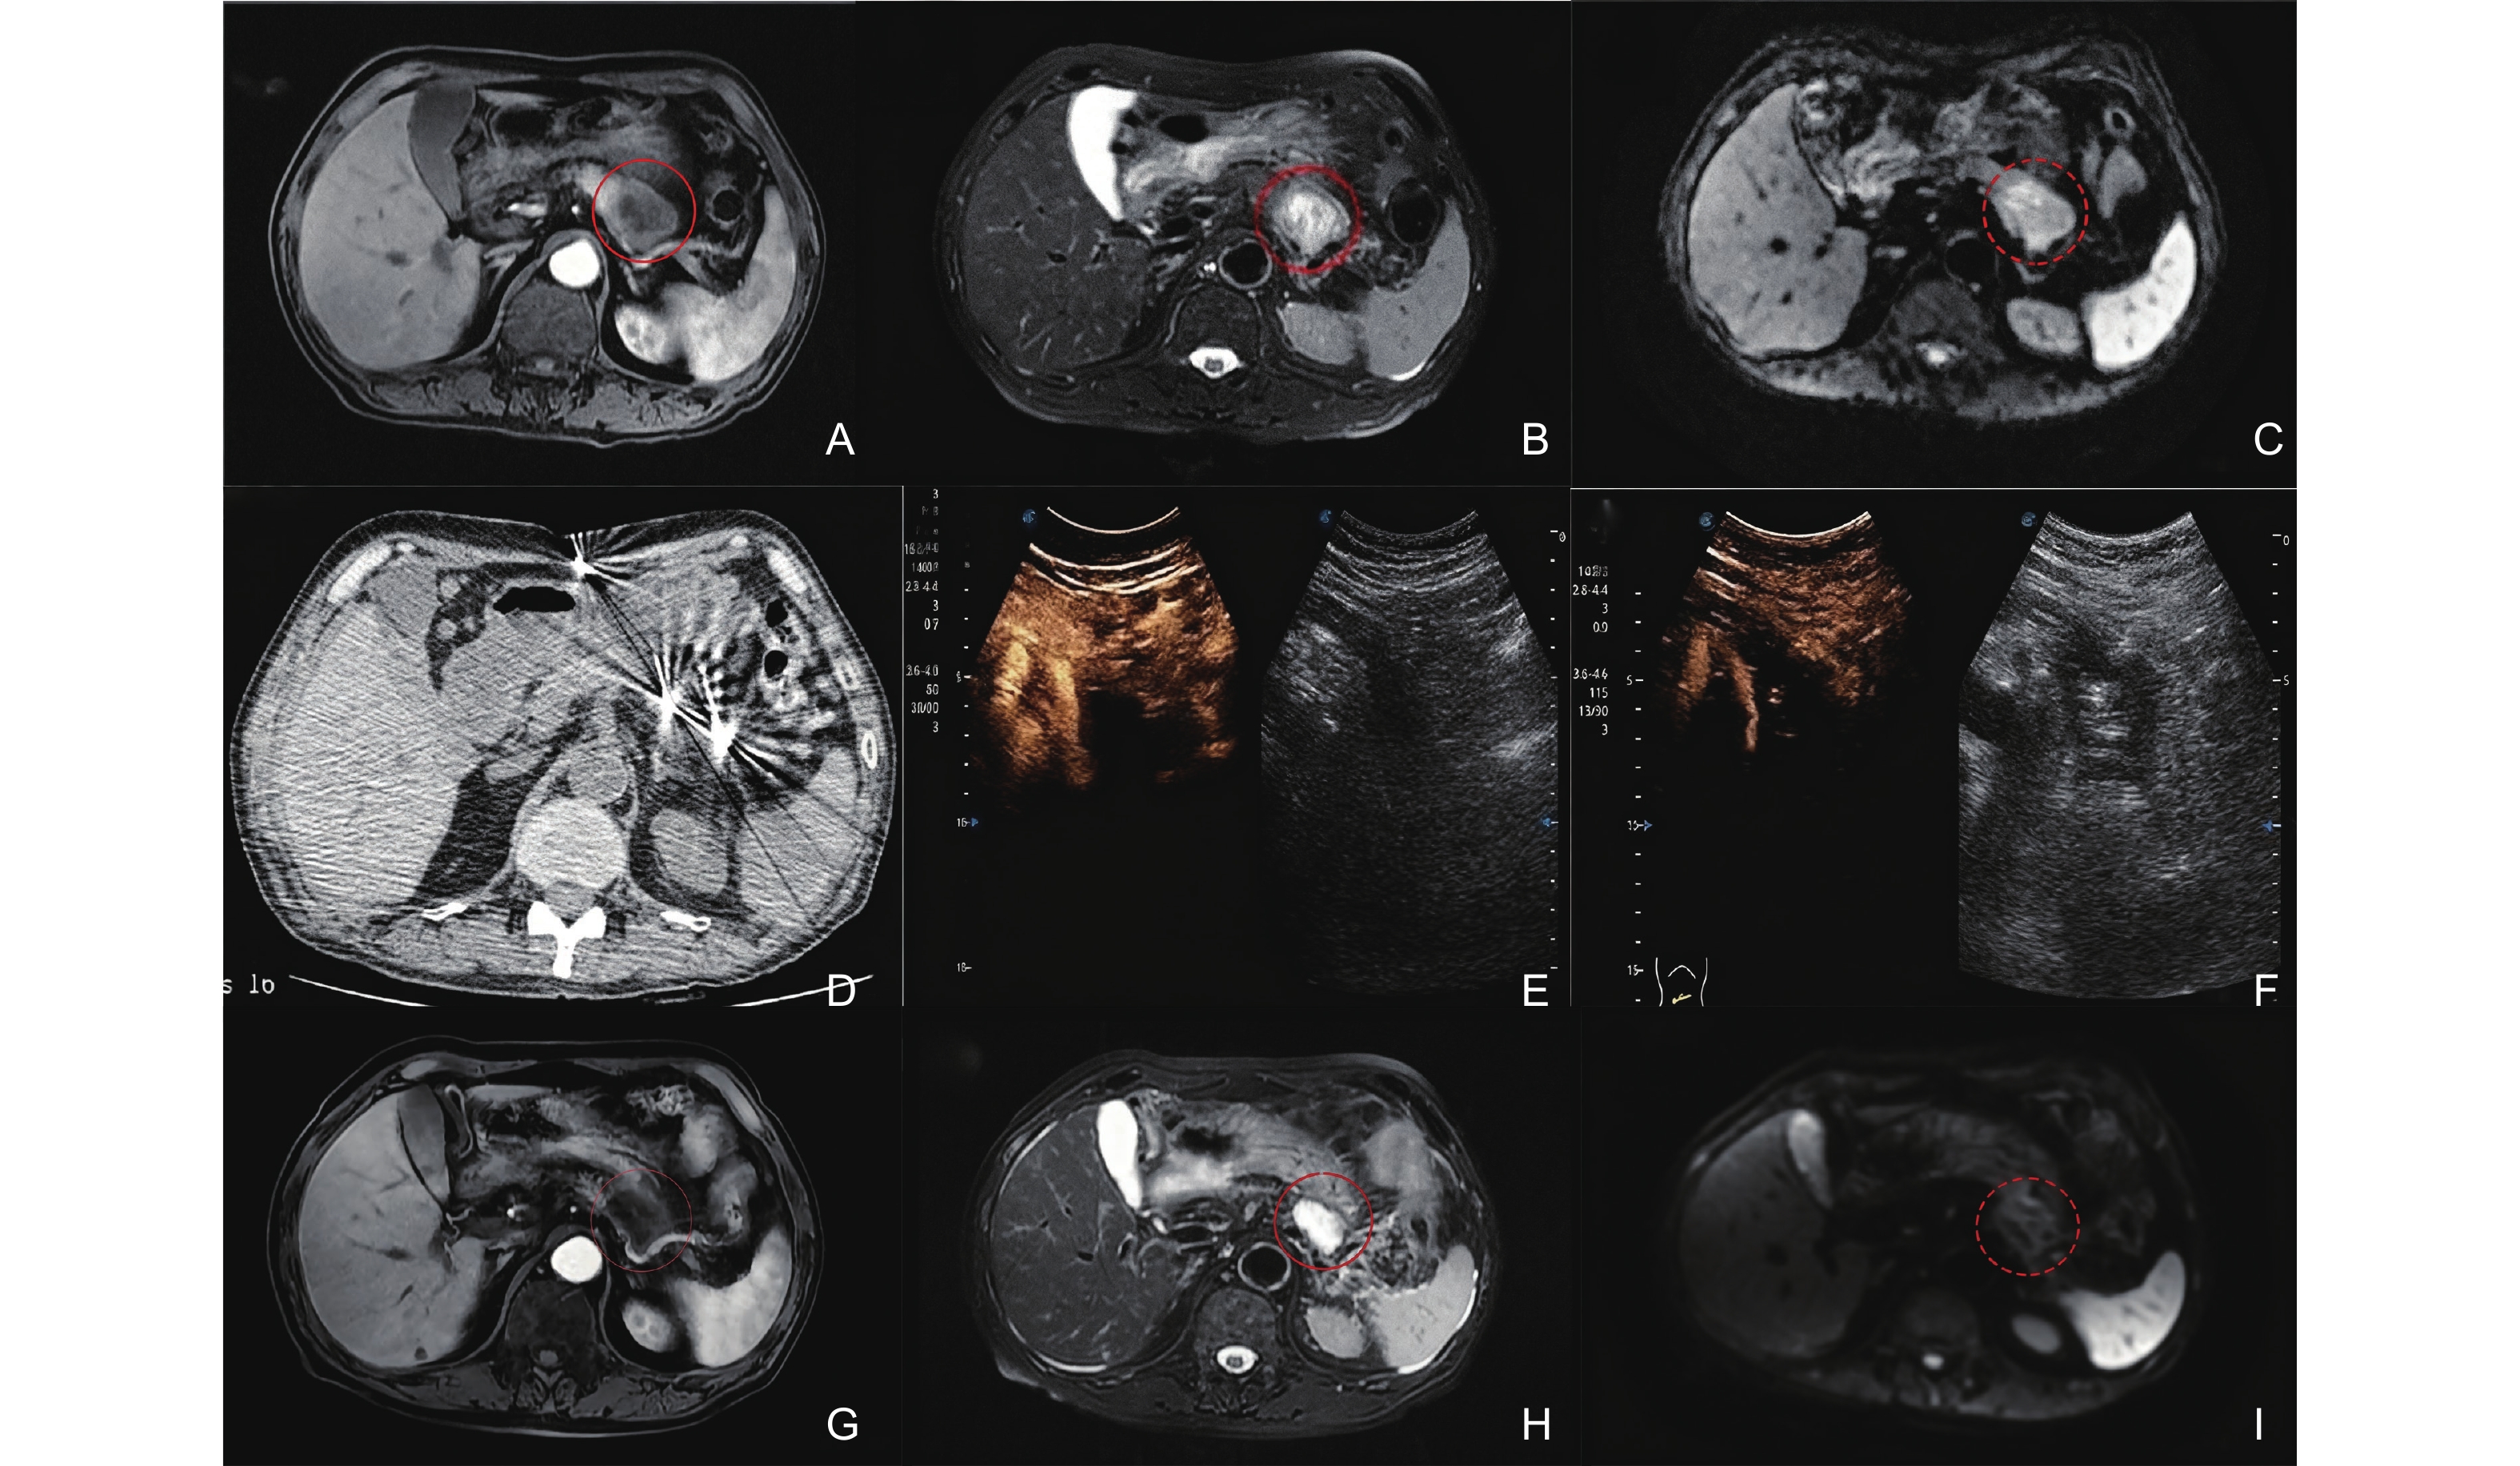

Figure 2

A 74-year-old male patient diagnosed with locally advanced pancreatic cancer (LAPC) presented with involvement of the body and tail of the pancreas, accompanied by gastric wall invasion, persisting for over five months. The patient exhibited advanced pancreatic cancer with distant metastasis, resulting in the loss of surgical intervention opportunities and failure of the initial chemotherapy regimen. Interventional sonographers and radiologists conducted ultrasound-guided, CT-assisted percutaneous irreversible electroporation (IRE) ablation for the cancers located in the pancreatic body and tail, administered under general anesthesia. A contrast-enhanced MRI of the pancreas was performed prior to the IRE procedure (images A, B, C). (A) T1-weighted image in the arterial phase shows a long T1 signal nodule (red circle) in the body and tail of the pancreas; (B) T2-weighted image shows that the lesion is a long T2 signal nodule (red circle); (C) DWI shows increased signal in the lesion (red circle). Intraoperative CT monitoring of needle placement combined with contrast-enhanced ultrasound to determine ablation range (images D, E, F). (D) The second and third IRE ablation needles are located on both sides below the lesion; (E) Preoperative contrast-enhanced ultrasound shows that the lesions in the pancreatic body and tail show lack of blood supply; (F) Immediate postoperative contrast-enhanced ultrasound shows that the pancreatic body A large non-enhancement area in the tail covers the target cancer, indicating complete ablation. Contrast-enhanced MRI of the pancreas 1 month after IRE (images G, H, I). (G) T1-weighted image in the arterial phase shows a long T1 signal nodule in the body and tail of the pancreas (red circle); (H) T2-weighted image shows that the lesion is a long T2 signal nodule (red circle); (I) DWI shows no abnormality in the signal of the lesion (red circle)."